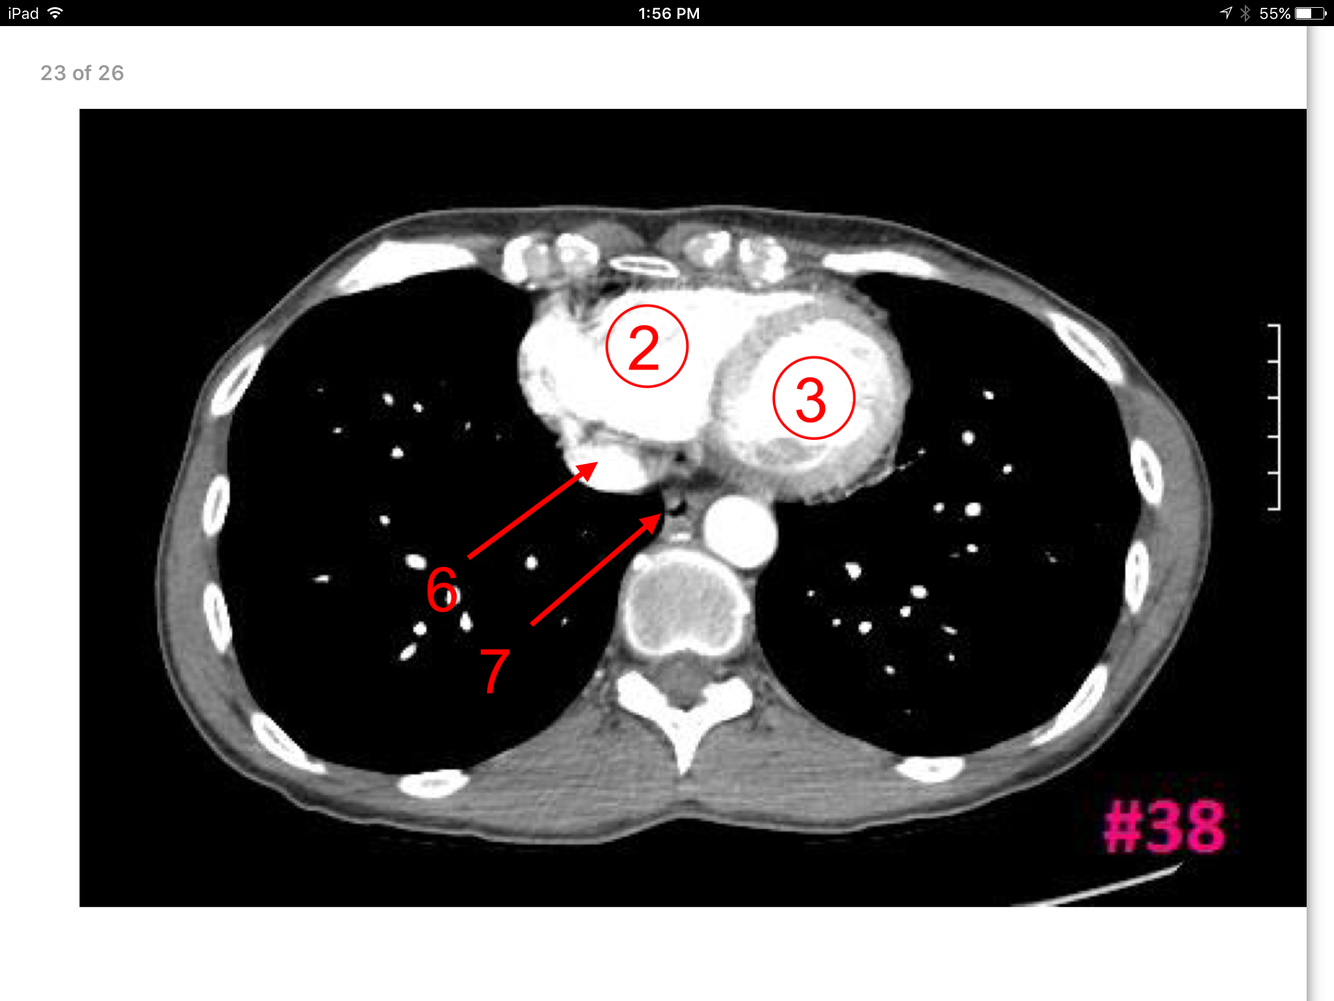

23

A

Rt ventricle

Lt ventricle

Inferior vena cava

Esophagus